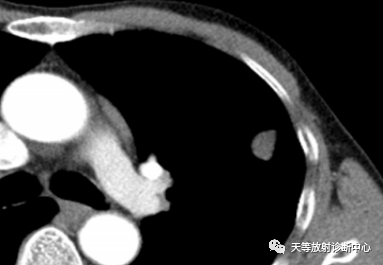

▲阻塞空洞型,由阻塞空洞充满干酪性物质形成,近端见支气管狭窄;